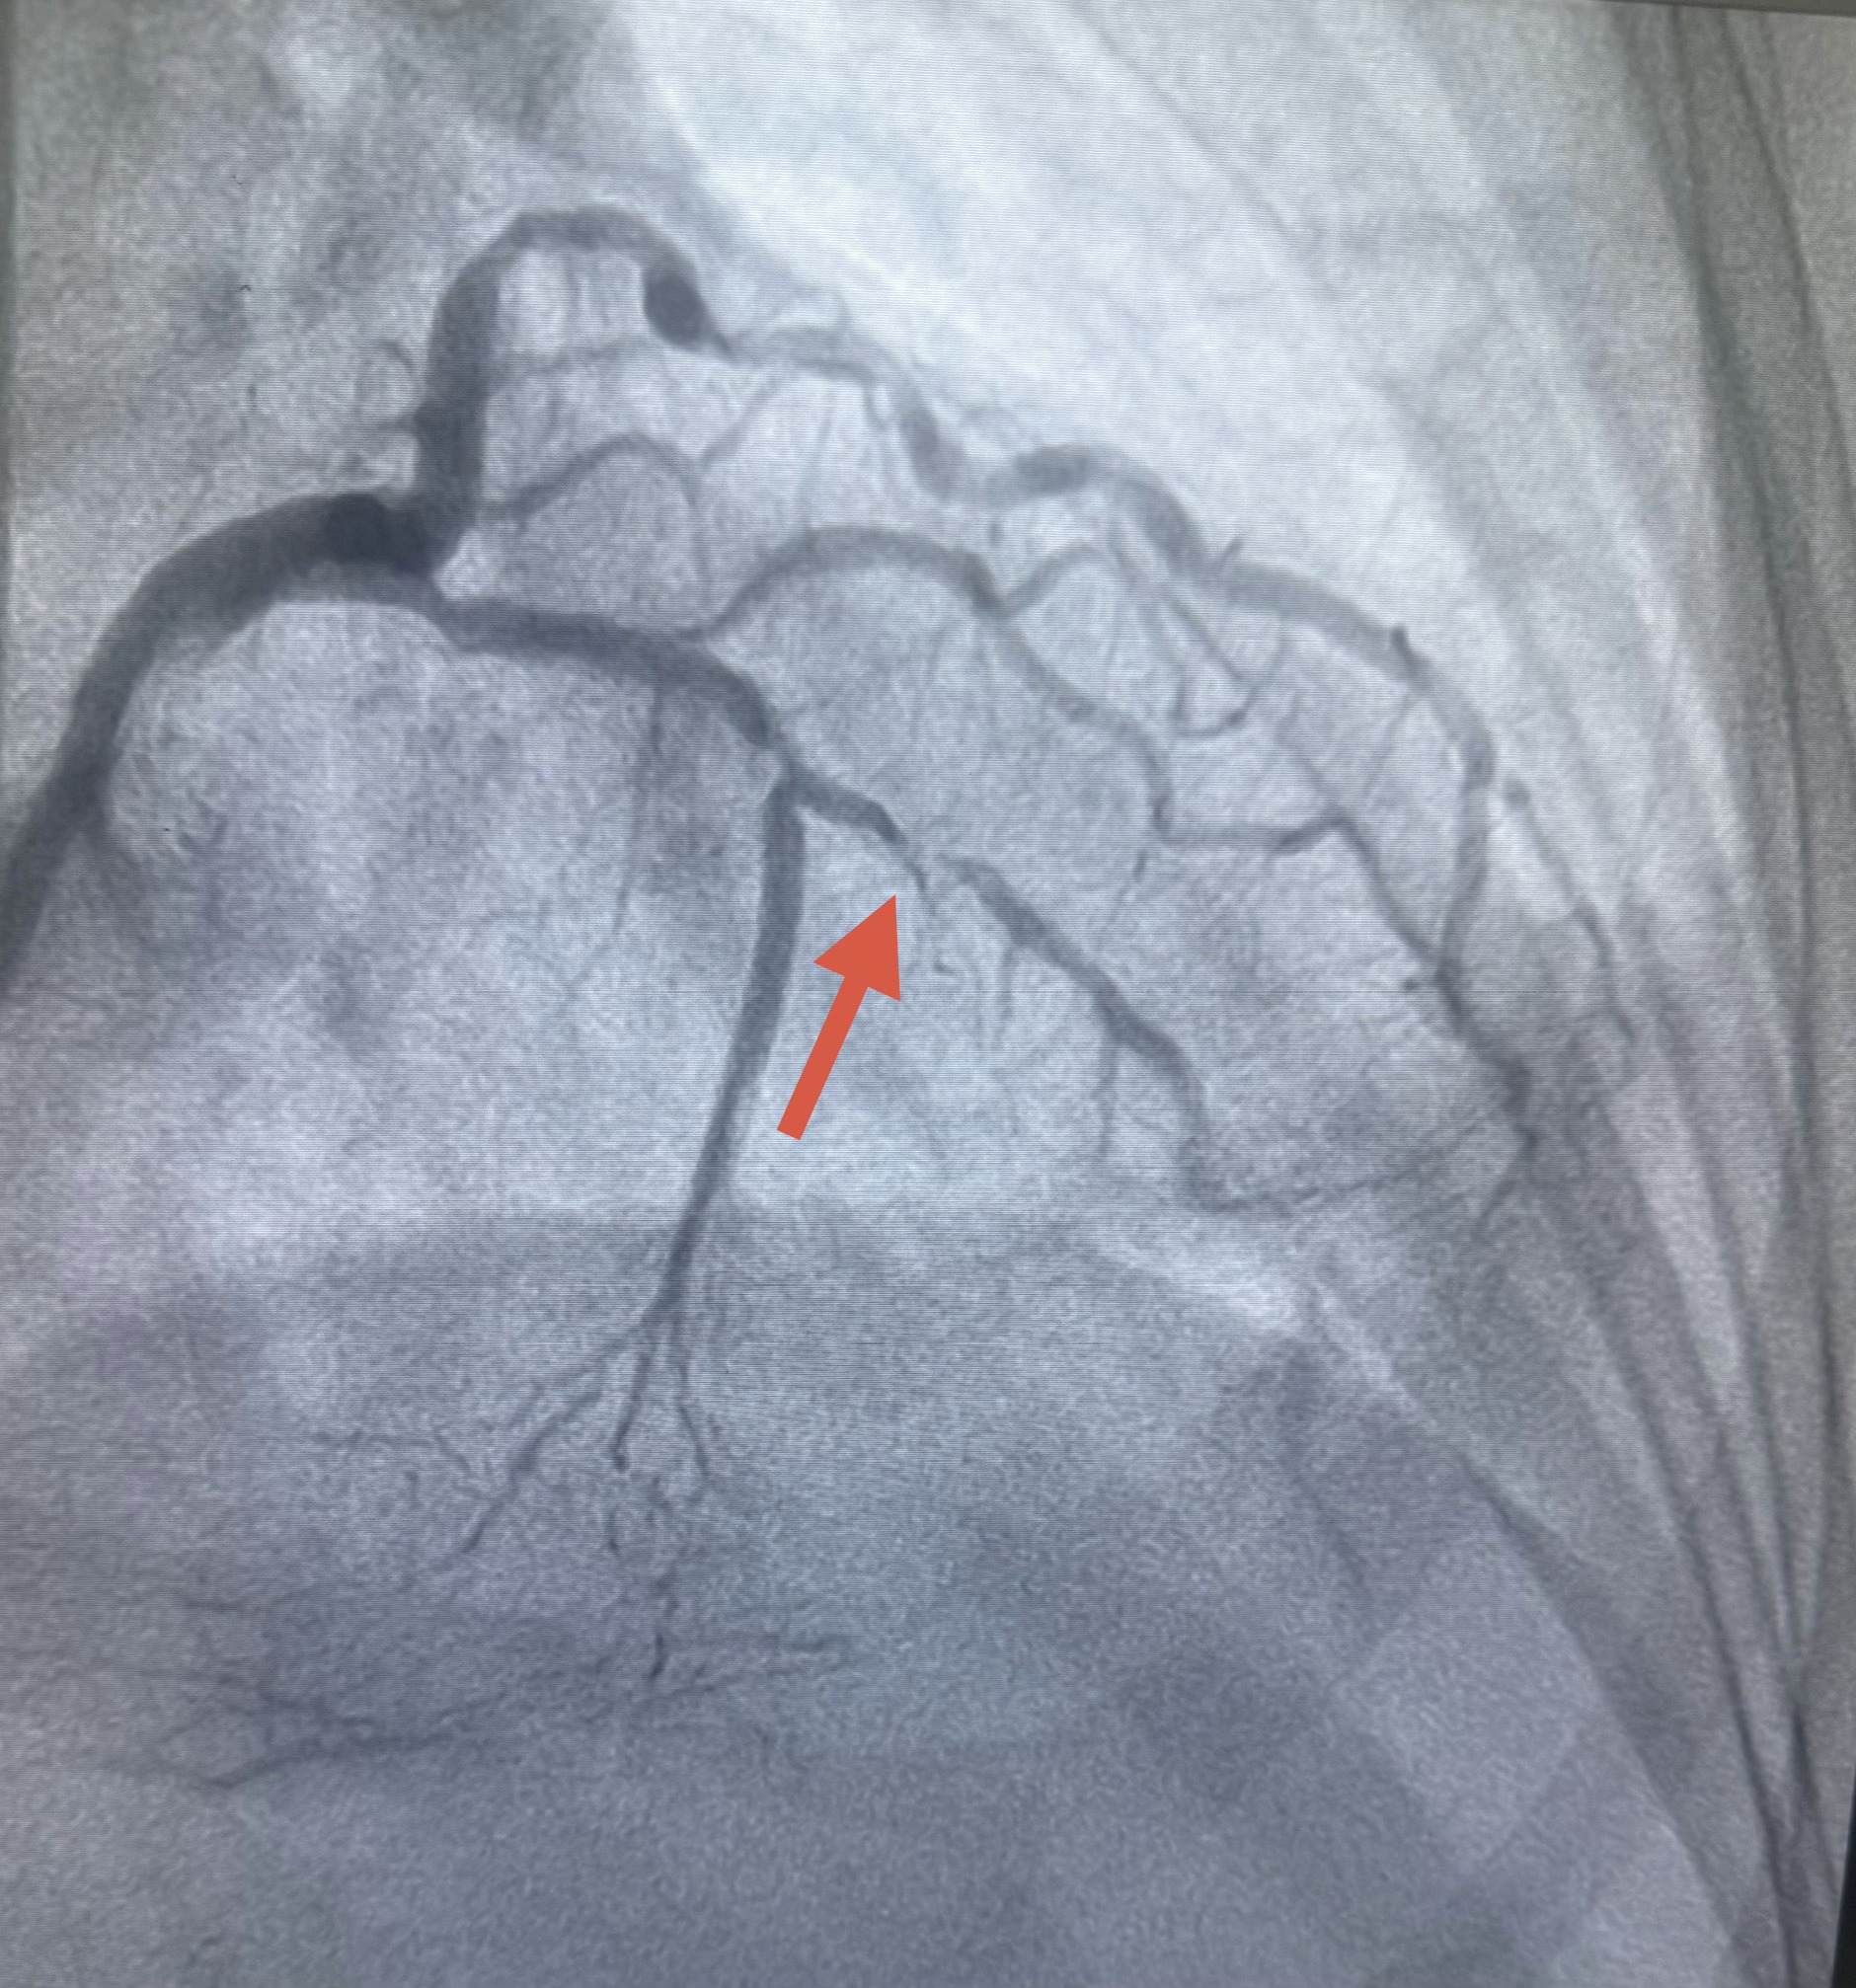

Bệnh nhân được chỉ định chụp mạch vành cấp cứu, kết quả cho thấy tổn thương bán tắc nhánh động mạch liên thất trước (LAD). Sau đó bệnh nhân được can thiệp mạch vành qua da đặt stent, tái thông dòng chảy mạch vành thành công. Sau thủ thuật, tình trạng lâm sàng cải thiện rõ rệt. Bệnh nhân hết đau đầu, hết cảm giác nặng ngực và hết đau vùng hàm, huyết động ổn định.